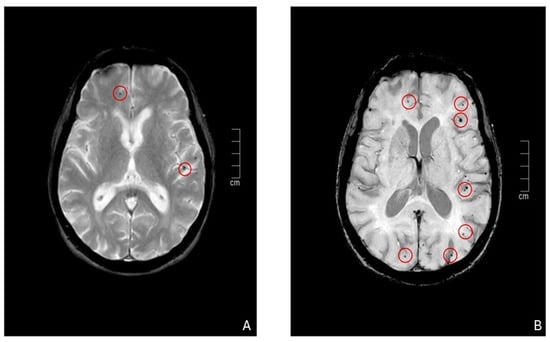

In De Sciscio et al. [14], a curve analysis of a ‘location-based’ ratio was obtained by calculating SWM/(SWM + strictly cortical CMBs) for patients who underwent CABG or valve replacement and for CAA patients. Indeed, most patients in both valve replacement and CABG groups had a lobar-restricted pattern (with a smaller proportion exhibiting a mixed pattern). A significant percentage of these patients mainly showed cortical/juxtacortical microbleeds, especially in the valve replacement group, while fewer microbleeds were found in the subcortical white matter. No significant differences regarding microbleed location or frequency were observed. When comparing the CMB burden in patients with CAA to those with post-surgical microbleeds, the CAA group exhibited a significantly higher load, particularly in cortical regions. For this reason, the authors conclude that the optimal “location-based ratio” to differentiate post-treatment CMBs from CAA might be approximately 0.45. Additionally, superficial siderosis was found in a significant proportion of CAA patients, while it was absent in those who underwent cardiac surgery [14] (Figure 5).

In summary, CAA typically presents in older patients with a history of lobar hemorrhages and cognitive decline, with MRI findings showing lobar microbleeds and cortical superficial siderosis. In contrast, perioperative microbleeds occur in the context of surgery, often associated with hemodynamic instability or microembolization. Radiologically, CAA exhibits a characteristic lobar distribution, while perioperative CMBs tend to show a more diffuse or non-specific pattern. Clinical history and timing relative to surgery are crucial for distinguishing between the two conditions.

Figure 5. Different CMB distributions (green arrows) in a patient who underwent endovascular surgery (A) versus a patient with CAA (B). Note the location of the microbleed in a lobar-restricted pattern in (A) while a prevalent cortical distribution with superficial hemosiderosis (yellow arrow) in the CAA patient.